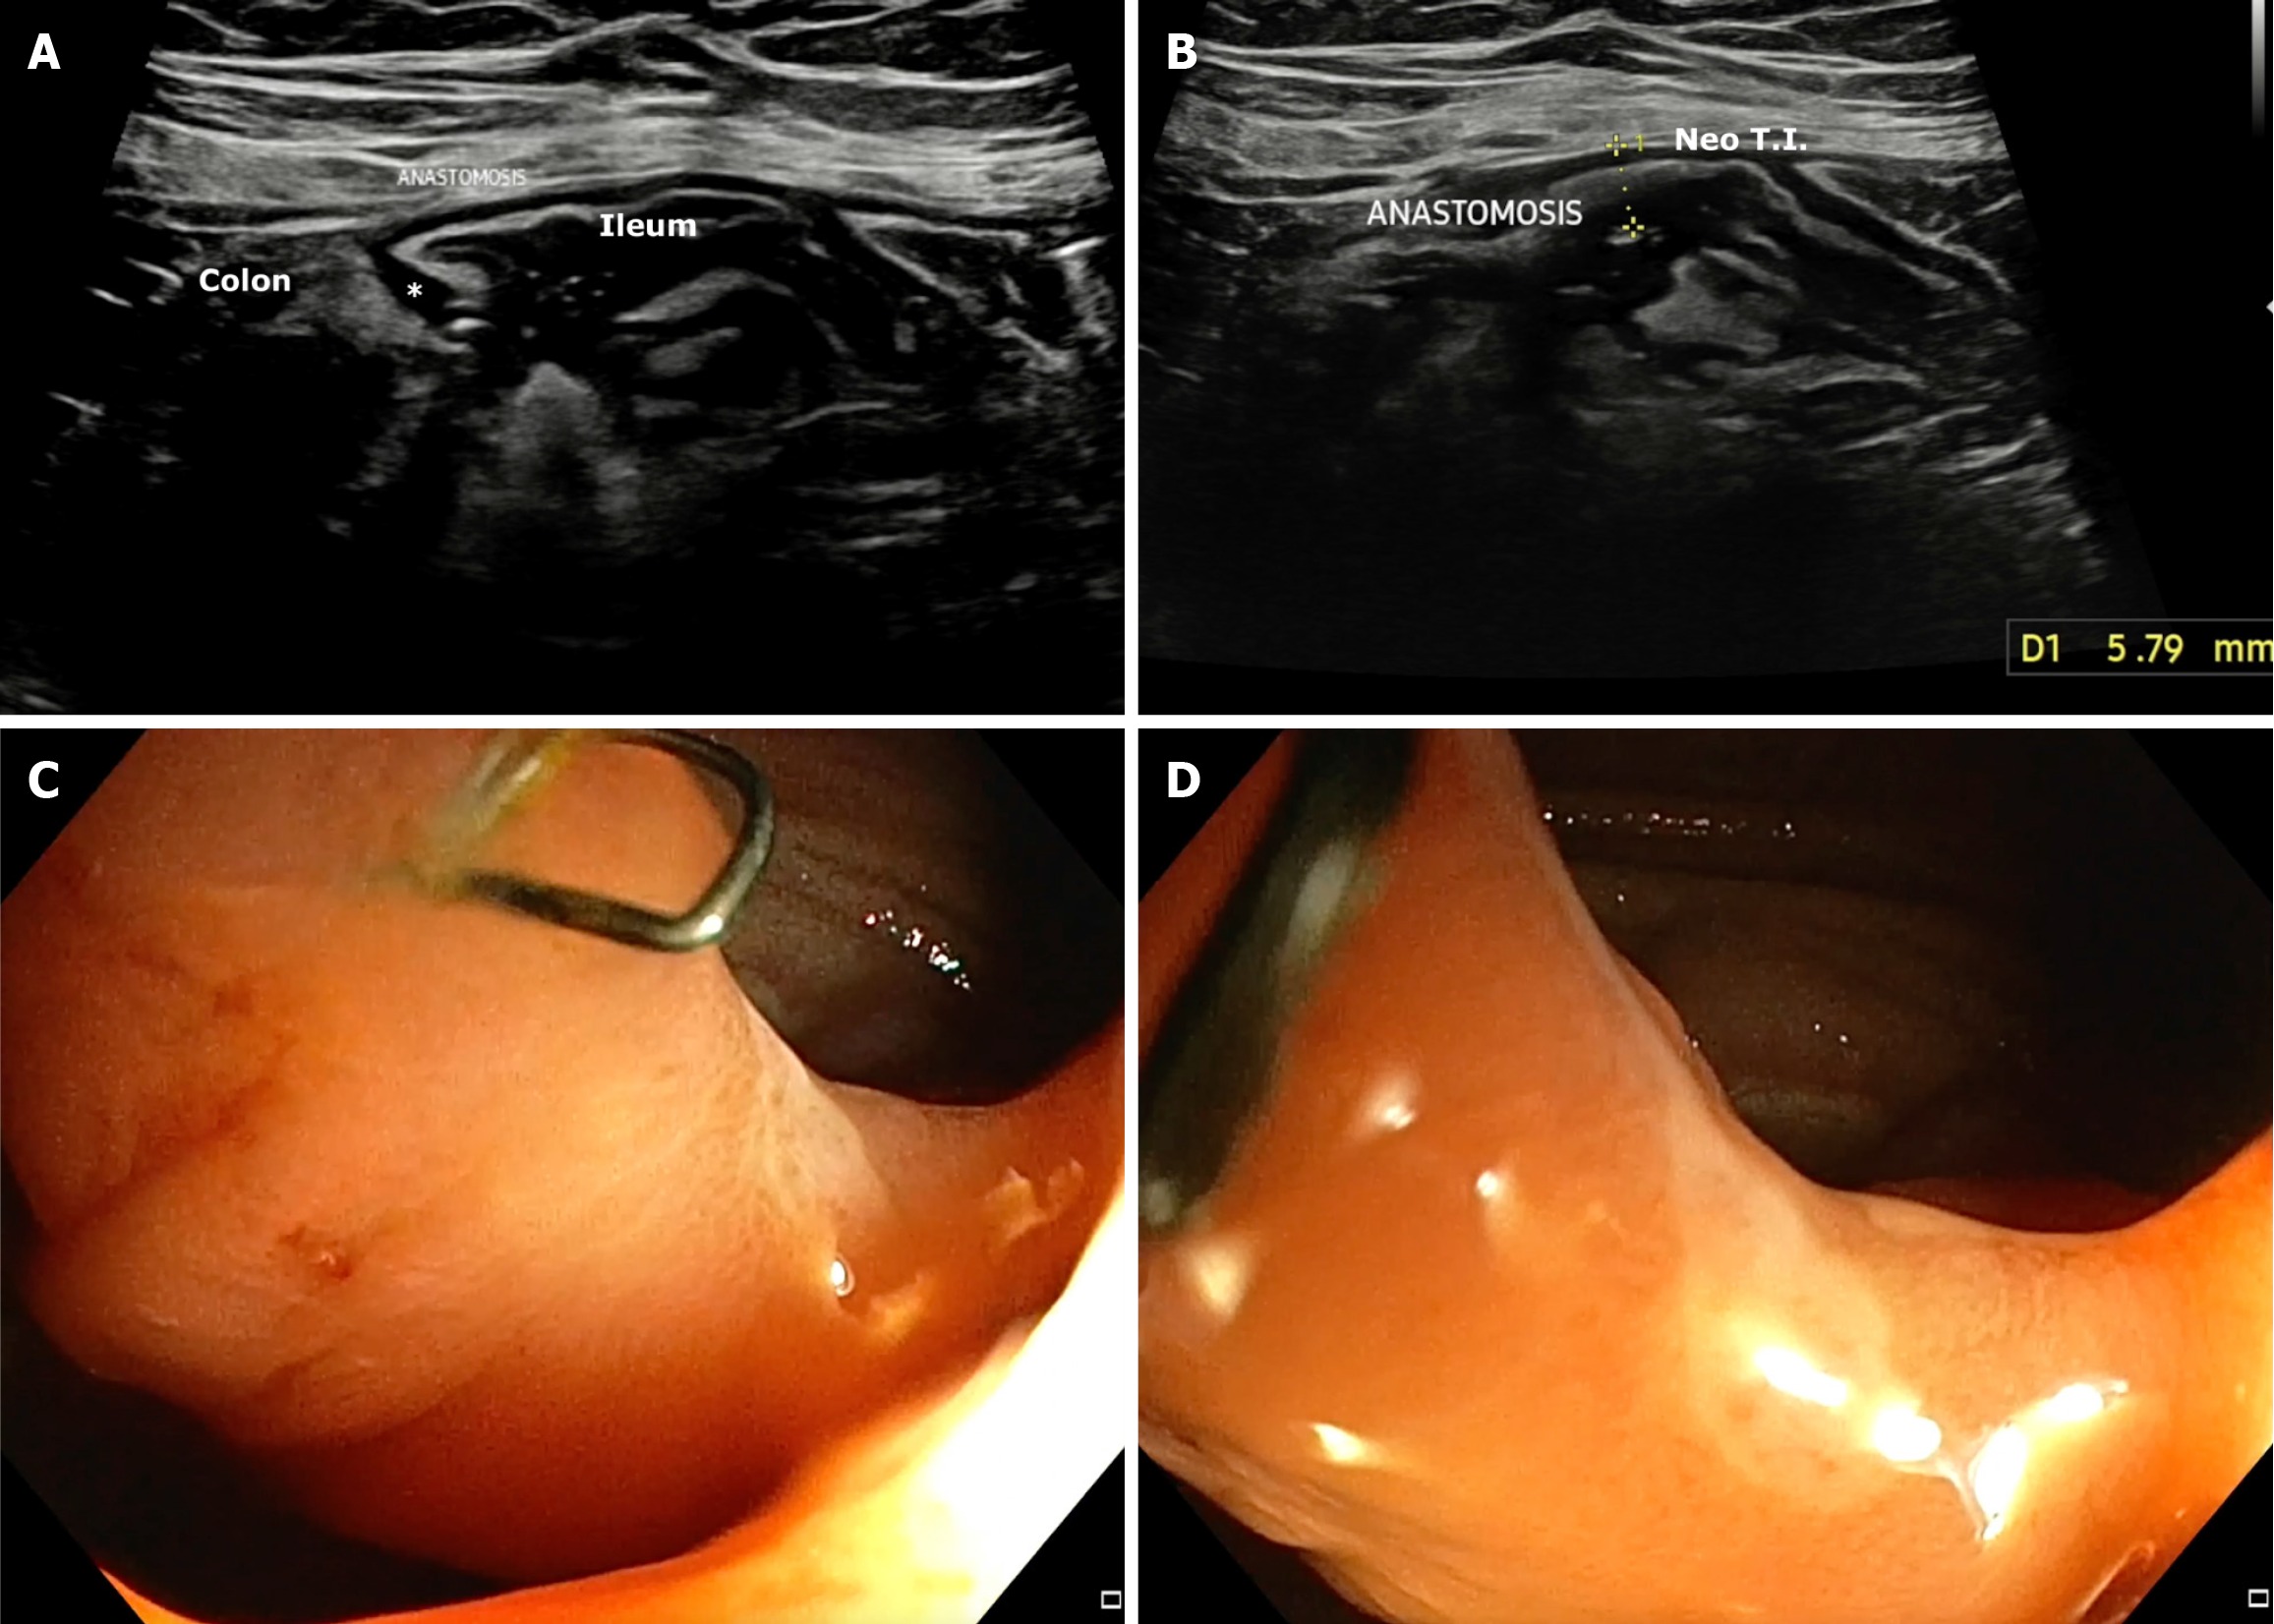

BWT: The role of IUS in predicting POR in CD has steadily evolved through a series of landmark studies, each building on prior findings (Table 1). The earliest, Andreoli et al[6], demonstrated that BWT > 5 mm in the neo-terminal ileum (NTI) strongly predicted endoscopic recurrence, with 81% sensitivity and 86% specificity (overall diagnostic accuracy 83%). This established a foundational BWT threshold and showed that IUS findings correlated well with endoscopic outcomes, even when measured within weeks of colonoscopy. Subsequently, Parente et al[1] added longitudinal perspective by showing that persistent or increased BWT (≥ 6 mm or < 40% reduction from baseline) at 12 months post-surgery was associated with a markedly elevated risk of symptomatic recurrence [hazard ratio (HR) = 8.9]. This study emphasized the value of serial monitoring over time and introduced echo pattern abnormalities (e.g., hypoechoic or mixed patterns) as independent predictors of poor outcomes. Rispo et al[7] focused on early prediction, showing that BWT > 5 mm within just 12 months postoperatively predicted severe endoscopic recurrence (Rutgeerts ≥ i3) with 94% sensitivity and 100% specificity (Figure 2). This reinforced BWT as a surrogate for endoscopic severity and highlighted its potential to replace ileocolonoscopic in high-risk patients. Cammarota et al[8] expanded the evidence to a larger retrospective cohort, showing that even modest thickening (BWT > 3 mm at the anastomotic site) was associated with an increased risk of surgical recurrence (relative risk = 2.1). Importantly, this study explored graduated BWT thresholds (> 3 mm, > 4 mm, > 5 mm, > 6 mm), demonstrating that risk increased incrementally with wall thickness, thus offering a framework for risk stratification. Across prospective studies, sensitivity for detecting endoscopic recurrence ranged from 77% to 94%, while specificity consistently exceeded 85%.

Dual-site assessment of BWT: While BWT at either the ileo-colonic anastomosis (ICA) or NTI independently predicts POR in CD, combining measurements from both sites significantly improves diagnostic accuracy. In a prospective cohort study, Pallotta et al[10] demonstrated that BWT > 3.5 mm at the ICA and > 3 mm at the NTI, when assessed together, yielded an area under the receiver operating characteristics curve of 0.95 for detecting endoscopic recurrence. This combined approach outperformed assessment at either site alone and supports the use of dual-site sonographic eva

Multiple studies have consistently validated the role of SICUS in detecting POR in CD through evaluation of BWT and other sonographic features (Table 3). Onali et al[12] demonstrated that SICUS could identify POR in all patients across 1-3 years of follow-up, though correlation with moderate-to-severe endoscopic recurrence (Rutgeerts ≥ 2) was limited. In a robust multicenter study, Pallotta et al[10] showed that BWT > 3.5 mm at the ICA predicted all cases of endoscopic recurrence, and when combined with measurement of neo-terminal ileal lesion length, it achieved an excellent discriminatory value (AUROC: 0.95). Similarly, Calabrese et al[13] reported a diagnostic accuracy of 92.5% using a BWT threshold of 3 mm. Castiglione et al[14] further reinforced the early predictive potential of SICUS, demonstrating high sensitivity (82%-94%) and specificity (> 90%) for recurrence detection within just 7 days post-resection. Finally, Onali et al[15] emphasized the long-term utility of SICUS in monitoring postoperative CD recurrence, proposing its integration into routine surveillance alongside or even in place of ileocolonoscopy. Together, these studies affirm that BWT - particularly at the anastomotic site - offers a reliable, non-invasive metric for tracking postoperative disease recurrence, with enhanced predictive accuracy when combined with lesion length and clinical correlation.